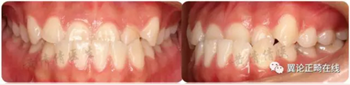

一個(gè)恒牙列早期的骨性3類小女生,沒(méi)有顯著家族遺傳史。

磨牙尖牙均為近中關(guān)系,前牙反覆頜較深,下切牙舌傾代償(IMPA=88.8度)。下頜可以功能性后退至切對(duì)切。

從軟組織面型上看,患者面中份發(fā)育尚可,面下1/3發(fā)育過(guò)度。下唇外翻明顯。

治療后咬合狀態(tài)、側(cè)貌、以及微笑弧等都得到很大改善。